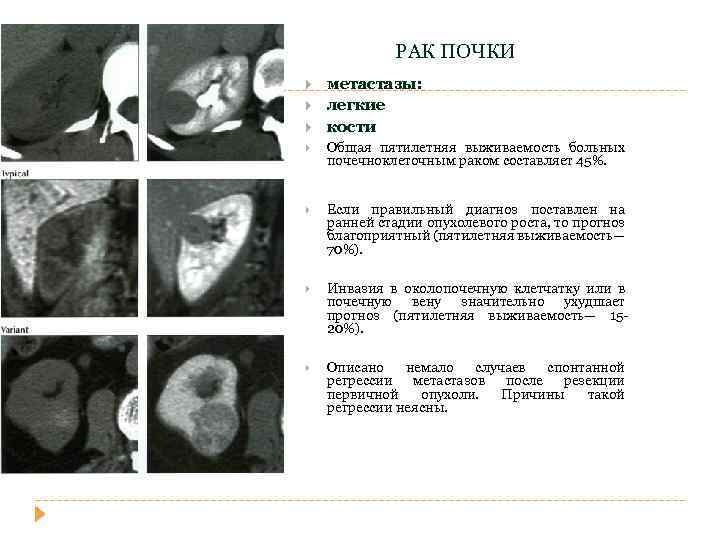

РАК ПОЧКИ метастазы: легкие кости Общая пятилетняя выживаемость больных почечноклеточным раком составляет 45%. Если правильный диагноз поставлен на ранней стадии опухолевого роста, то прогноз благоприятный (пятилетняя выживаемость— 70%). Инвазия в околопочечную клетчатку или в почечную вену значительно ухудшает прогноз (пятилетняя выживаемость— 1520%). Описано немало случаев спонтанной регрессии метастазов после резекции первичной опухоли. Причины такой регрессии неясны.